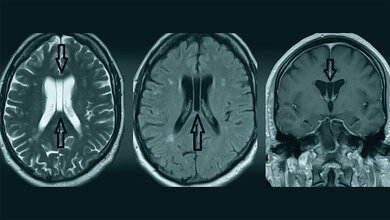

Der Maldescensus testis ist die häufigste genitale Malformation der Jungen und hat ein erhöhtes Risiko der Infertilität und malignen Entartung. Die Therapie mit humanem Choriongonadotropin ist oft erfolgreich, sonst die operative Behandlung mit Orchiopexie.

Schlüsselwörter: Maldescensus testis, Röntgen, Sonografie, CT, MRT